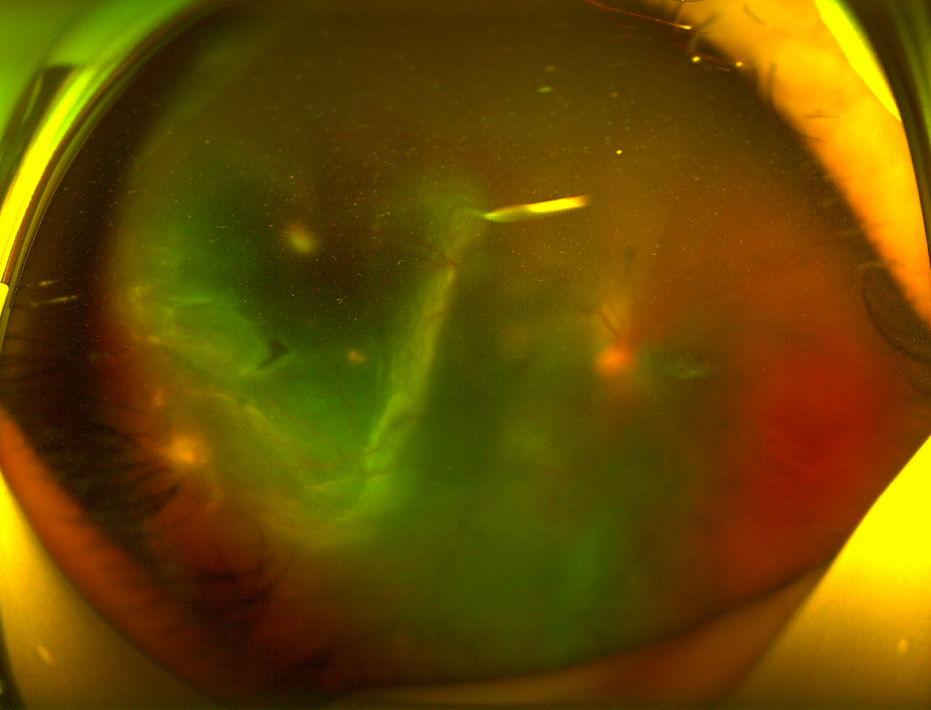

✅角膜形态稳定,晶状体无进行性混浊,玻璃体无增殖性病变,黄斑及周边视网膜无活动性病变。